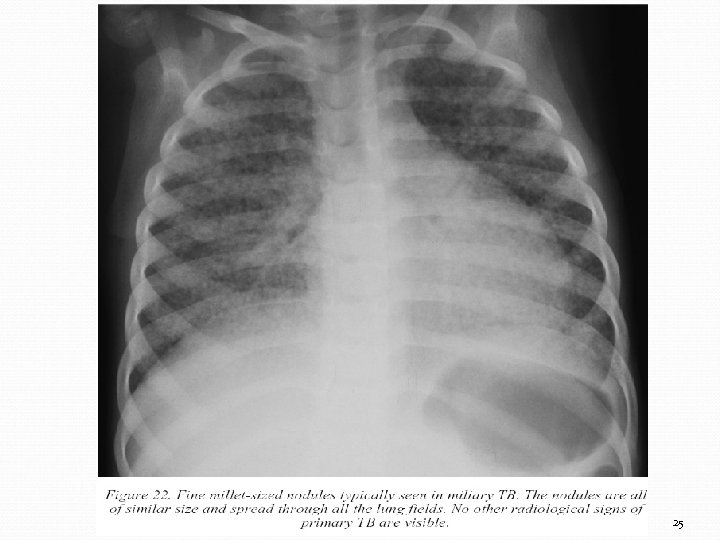

25

Diagnostic Test à la tuberculine (positif dans 0 -30%) Radiographie utile dans les cas de suspicion de TB pulmonaire ou miliaire Diagnostic microbiologique Frottis d’aspirations gastriques, crachat induit, LCR ou autres liquides corporels (immunofluorescence plus sensible) Cultures (milieu L-J, système bactec ~ 2 semaines) Diagnostic histologique Techniques moléculaires (PCR, Sérologie) 21